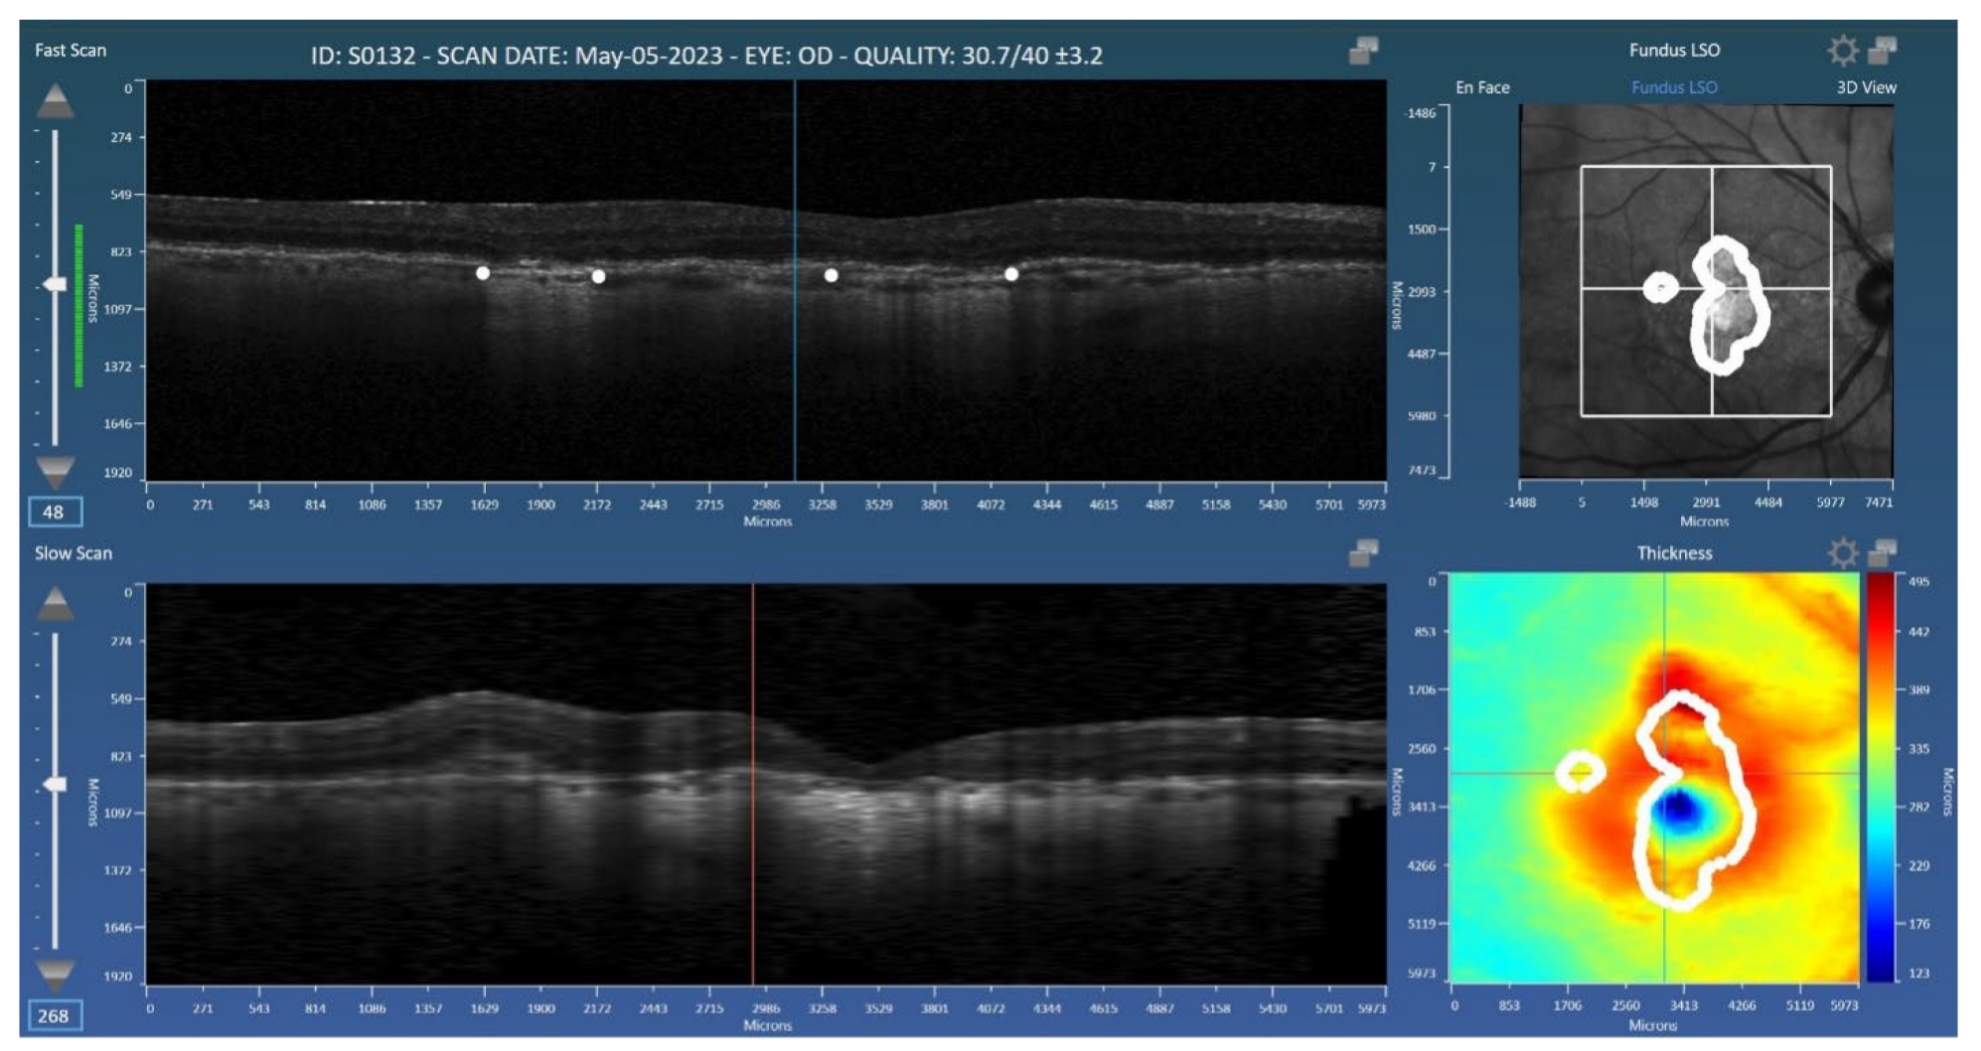

- Voiant announces the publication of a peer-reviewed study in Diagnostics demonstrating a deep learning-based method for automated geographic atrophy (GA) quantification in SD-OCT imaging.

Voiant, a leader in clinical trial imaging solutions, is pleased to announce the publication of a new peer-reviewed study in Diagnostics as part of the Special Issue Updates on the Diagnosis and Management of Retinal Diseases—2nd Edition. The article, titled “Deep Learning-Based Segmentation of Geographic Atrophy: A Multi-Center, Multi-Device Validation in a Real-World Clinical Cohort“, presents a deep learning-based method for automated segmentation and quantification of geographic atrophy (GA) in spectral-domain optical coherence tomography (OCT) scans.

The model was trained and validated on real-world clinical data from two major OCT platforms (Spectralis and Cirrus) among patients with and without concurrent neovascular age-related macular degeneration (nAMD). Results from the Spectralis and Cirrus data sets achieved Dice similarity coefficient (DSC) scores of 0.83 and 0.82, respectively, and correlation coefficients (r2) of 0.91 and 0.88, respectively, with manual expert grading. The study concludes that deep learning offers accurate, reproducible GA assessment across diverse imaging conditions and comorbidities. Read the full open-access paper here for more information.

The research leverages Orion, Voiant’s cloud-based reading platform developed by Voxeleron, a Voiant Company. Orion supports flexible reading center workflows with advanced editing tools, native file format compatibility, and automated segmentation for retinal layers, GA, and fluid regions. The purpose-built software enables multimodal analysis tools that are validated, reproducible, and tailored to sponsor needs.